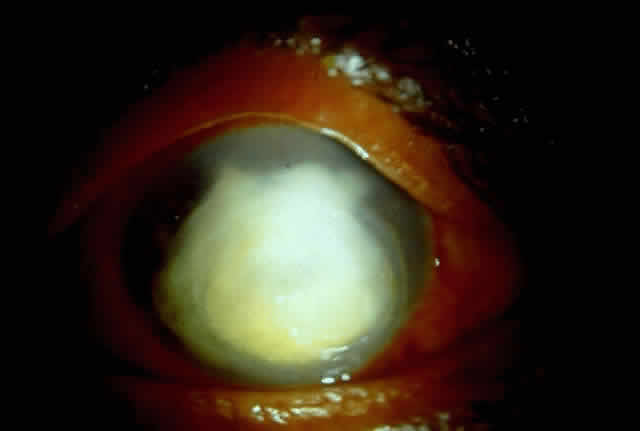

Fungal keratitis is as frequently seen as bacterial keratitis. Aspergillus and Fusarium are the two most commonly isolated organisms. Predisposing factors include trauma, foreign body, and injudicious usage of topical steroids or other indigenous medications.

Delay in diagnosis, the relative ineffectiveness of antifungal agents in most parts of the world, and the nonavailability of these drugs hinder prevention and management (Fig. 3).

|